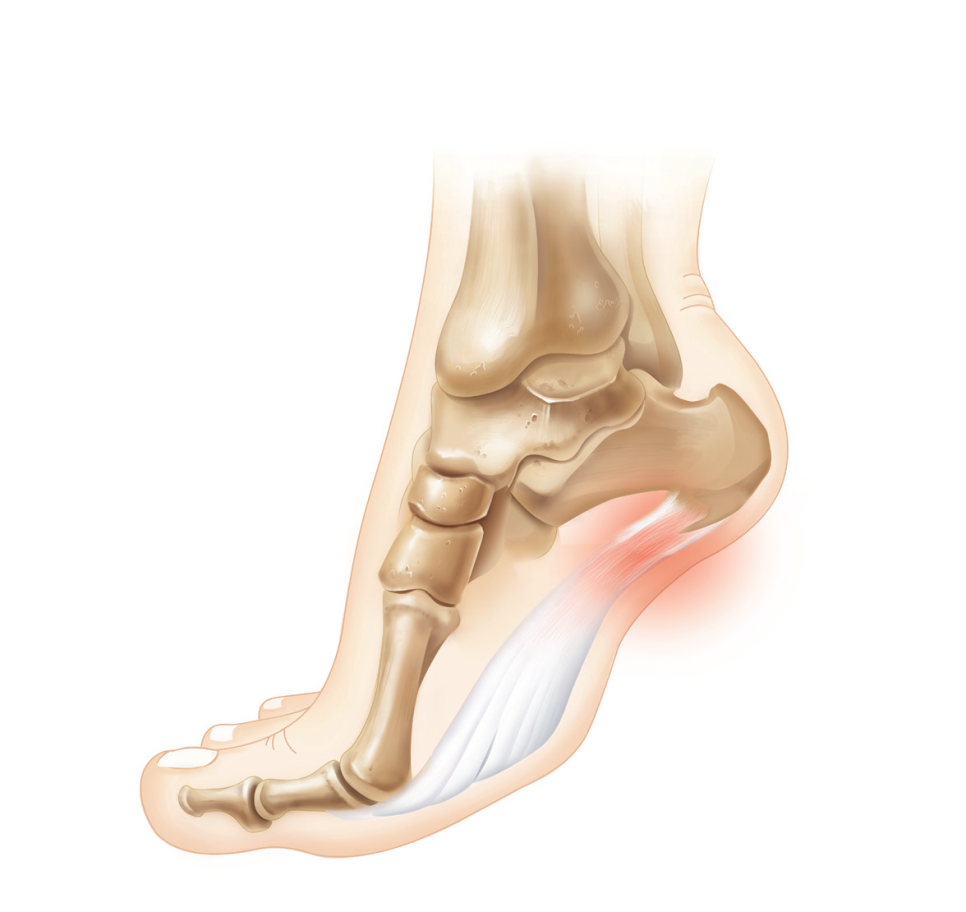

□ 발바닥 근막이 종골 기시부에서 반복적인 미세손상을 입어 발뒤꿈치로 통증이 나타나는 것을 말합니다.

□ 종골의 내측 및 발 안쪽을 따라 발생하는 통증과 압통을 특징으로 합니다.

□ 특히 아침에 일어나 처음 발을 디딜 때 심한 통증이 나타납니다.

□ 진행될 경우 걷는 데 문제가 발생하여 무릎, 고관절, 척추에 문제를 일으킬 수 있습니다.